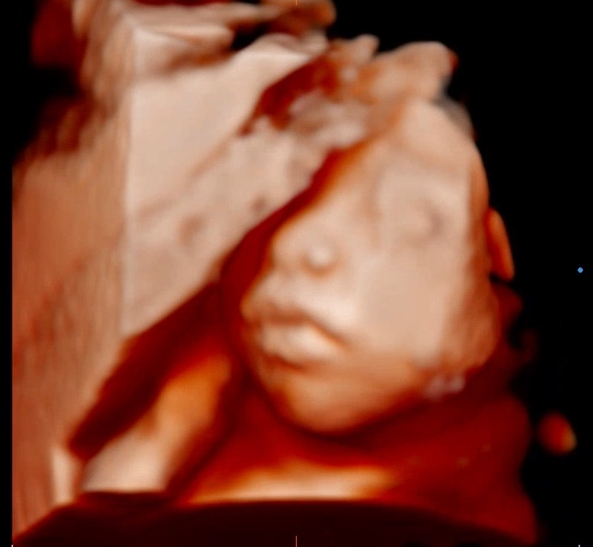

27주 5일: 입체초음파, 심장소리, 태아 몸무게, 이목구비

7월 24일, 이 날은 두 번째 입체초음파가 예정되어 있는 날 항상 함께 방문하던 산부인과이지만 회사에 일 ...